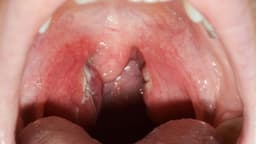

Viêm lộ tuyến cổ tử cung là bệnh phụ khoa rất phổ biến ở nữ giới. Bệnh không chỉ gây đau đớn, mệt mỏi mà còn ảnh hưởng đến việc thụ thai, gây sảy thai hoặc sinh non… Bài viết dưới đây là những điều cần biết về viêm lộ tuyến cổ tử cung 1. […]

Viêm cổ tử cung là dạng tổn thương cổ tử cung thường gặp. Tùy vào mức độ tổn thương mà người ta chia viêm cổ tử cung thành 2 dạng là viêm cổ tử cung cấp tính và viêm cổ tử cung mạn tính. Vậy viêm cổ tử cung là gì? Triệu chứng nào cảnh […]